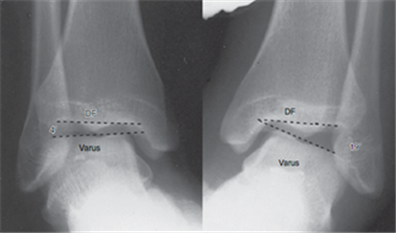

발목 불안정성 여부를 확인하기 위해서는 검진 의사가 스트레스를 가하면서 손의 감각으로 발목의 느슨한 정도를 주관적으로 느끼는 이학적 검사와 스트레스 X-ray 촬영을 함께 합니다. 스트레스 X-ray 검사를 통해 발목 외측이 많이 벌어진다면 발목 외측 불안정성을 의심할 수 있습니다. 반대편 발목과 함께 시행해 비교하면 개개인마다 다른 관절 유연성을 배제하면서 평가할 수 있다는 장점이 있습니다.

다만, 환자가 검사 시에 통증을 느껴 발목에 힘을 줄 경우 검사 결과가 부정확할 수 있는 단점이 있습니다. 발목 인대를 직접 관찰해야 할 경우나 건 손상, 골연골 병변 등의 동반 손상을 찾기 위해서는 MRI 검사를 추가로 시행하게 됩니다.